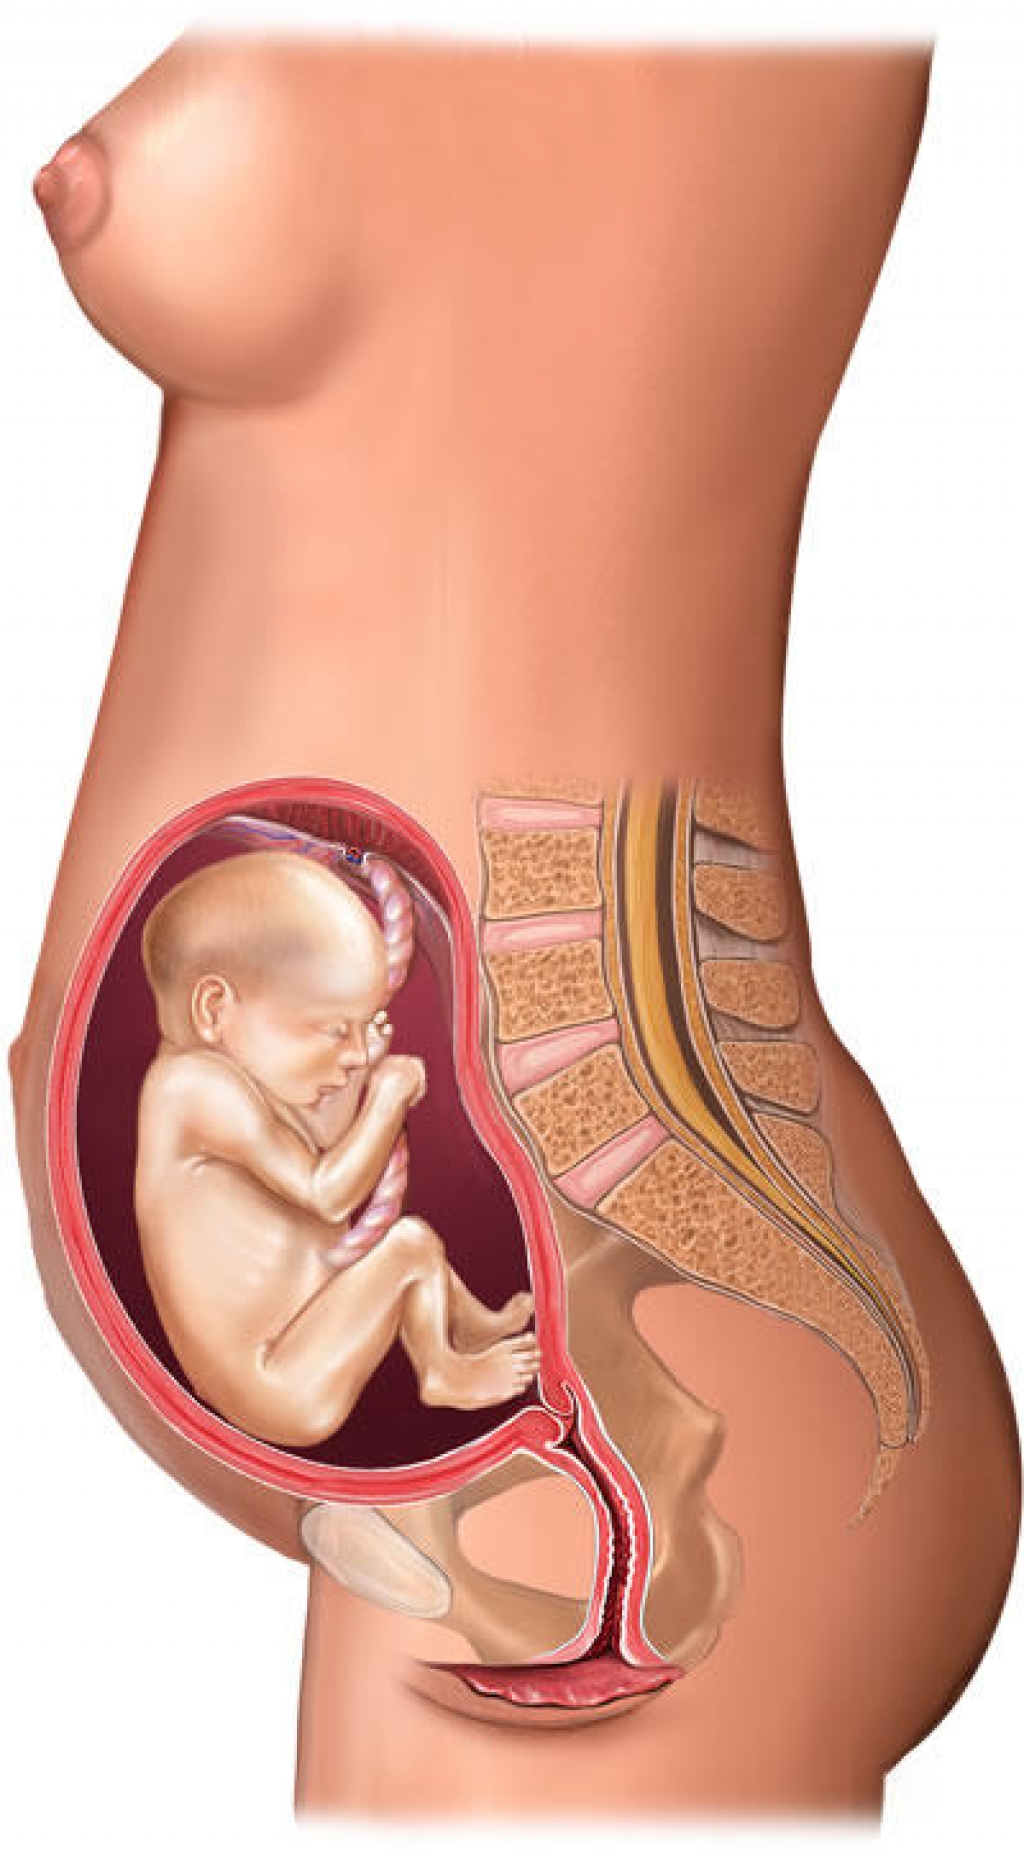

Важный этап: развитие малыша на 20-й неделе беременности